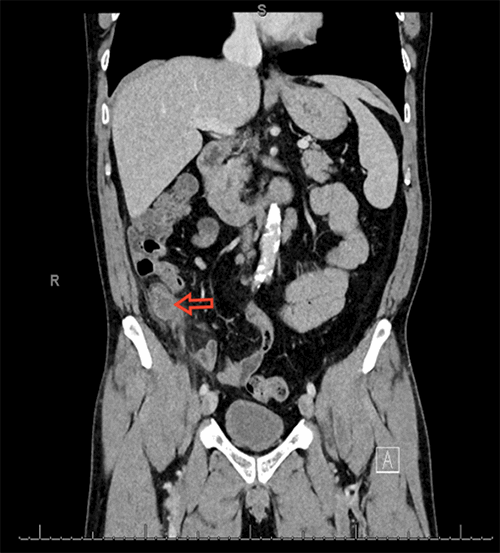

A 57-year-old Caucasian male presented with a two-week history of progressively worsening right lower quadrant abdominal pain, nausea, and vomiting. He also endorsed an associated fever, diarrhea, and anorexia. Computed tomography of the abdomen and pelvis was remarkable for a markedly dilated appendix, measuring up to 20 mm, with wall thickening and surrounding inflammatory changes, suggesting acute appendicitis (Figure 1).

Figure 1. CT of the abdomen and pelvis with contrast, coronal view. Dilated appendix with significant wall thickening and inflammatory changes (arrow).